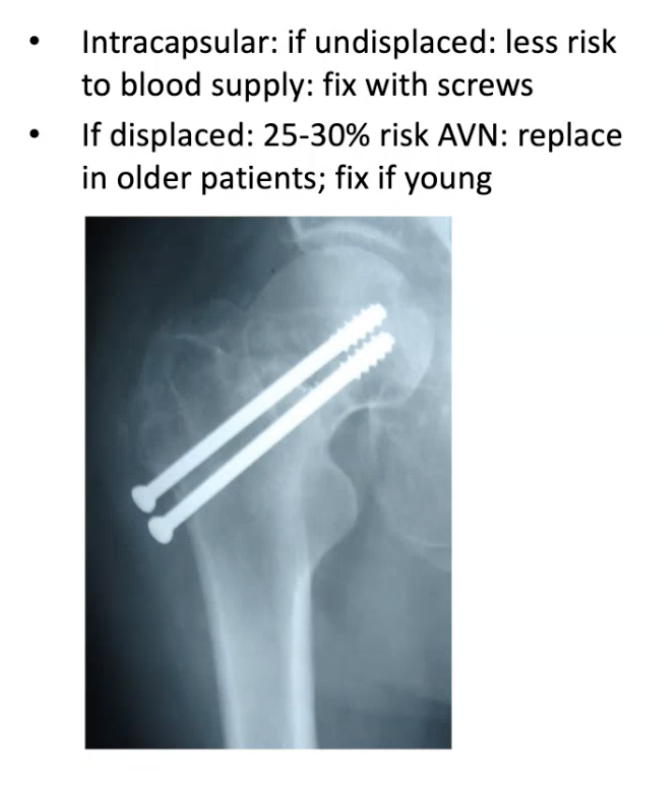

14

Q

What is the general management for undisplaced intracapsualr NOF?

A

Screws

(less risk of avascular necrosis due to no displacement)

15

What is the management of displaced intracapsular NOF fractures?

Depending on patient